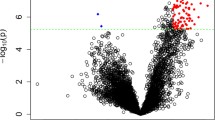

To investigate immune infiltration in SCZ, we employed the ssGSEA method to evaluate the presence of 26 distinct immune cell types within the substantia nigra of SCZ and control samples. We found significantly higher levels of activated CD8+ T cells, effector memory CD4+ T cells, mast cells, naïve CD8+ T cells, peripheral blood mononuclear cells (PBMC), Th17, central memory CD8+ T cells, CD56 bright NK cells, memory B cells, and regulatory T cells in the SCZ group compared to the control group (Fig. 3). Conversely, immature dendritic cell (dc) infiltration was lower in patients with SCZ across various immune cell types. Our immune infiltration analysis revealed 10 distinct infiltrating immune cell types between SCZ and control samples. These cell types include activated CD8+ T cells, effector memory CD4+ T cells, mast cells, naive CD8+ T cells, peripheral blood mononuclear cells (PBMC), type 17 helper cells (Th17), central memory CD8+ T cells, CD56 bright NK cells, memory B cells, and regulatory T cells. Finally, nine hub genes were eliminated using LASSO logistic regression: ASGR2, ADRM1, AHANK, S100A8, FUCA1, AKNA, GATA3, AHCYL2, and PTRH2.

Immune Infiltration Analysis in SCZ